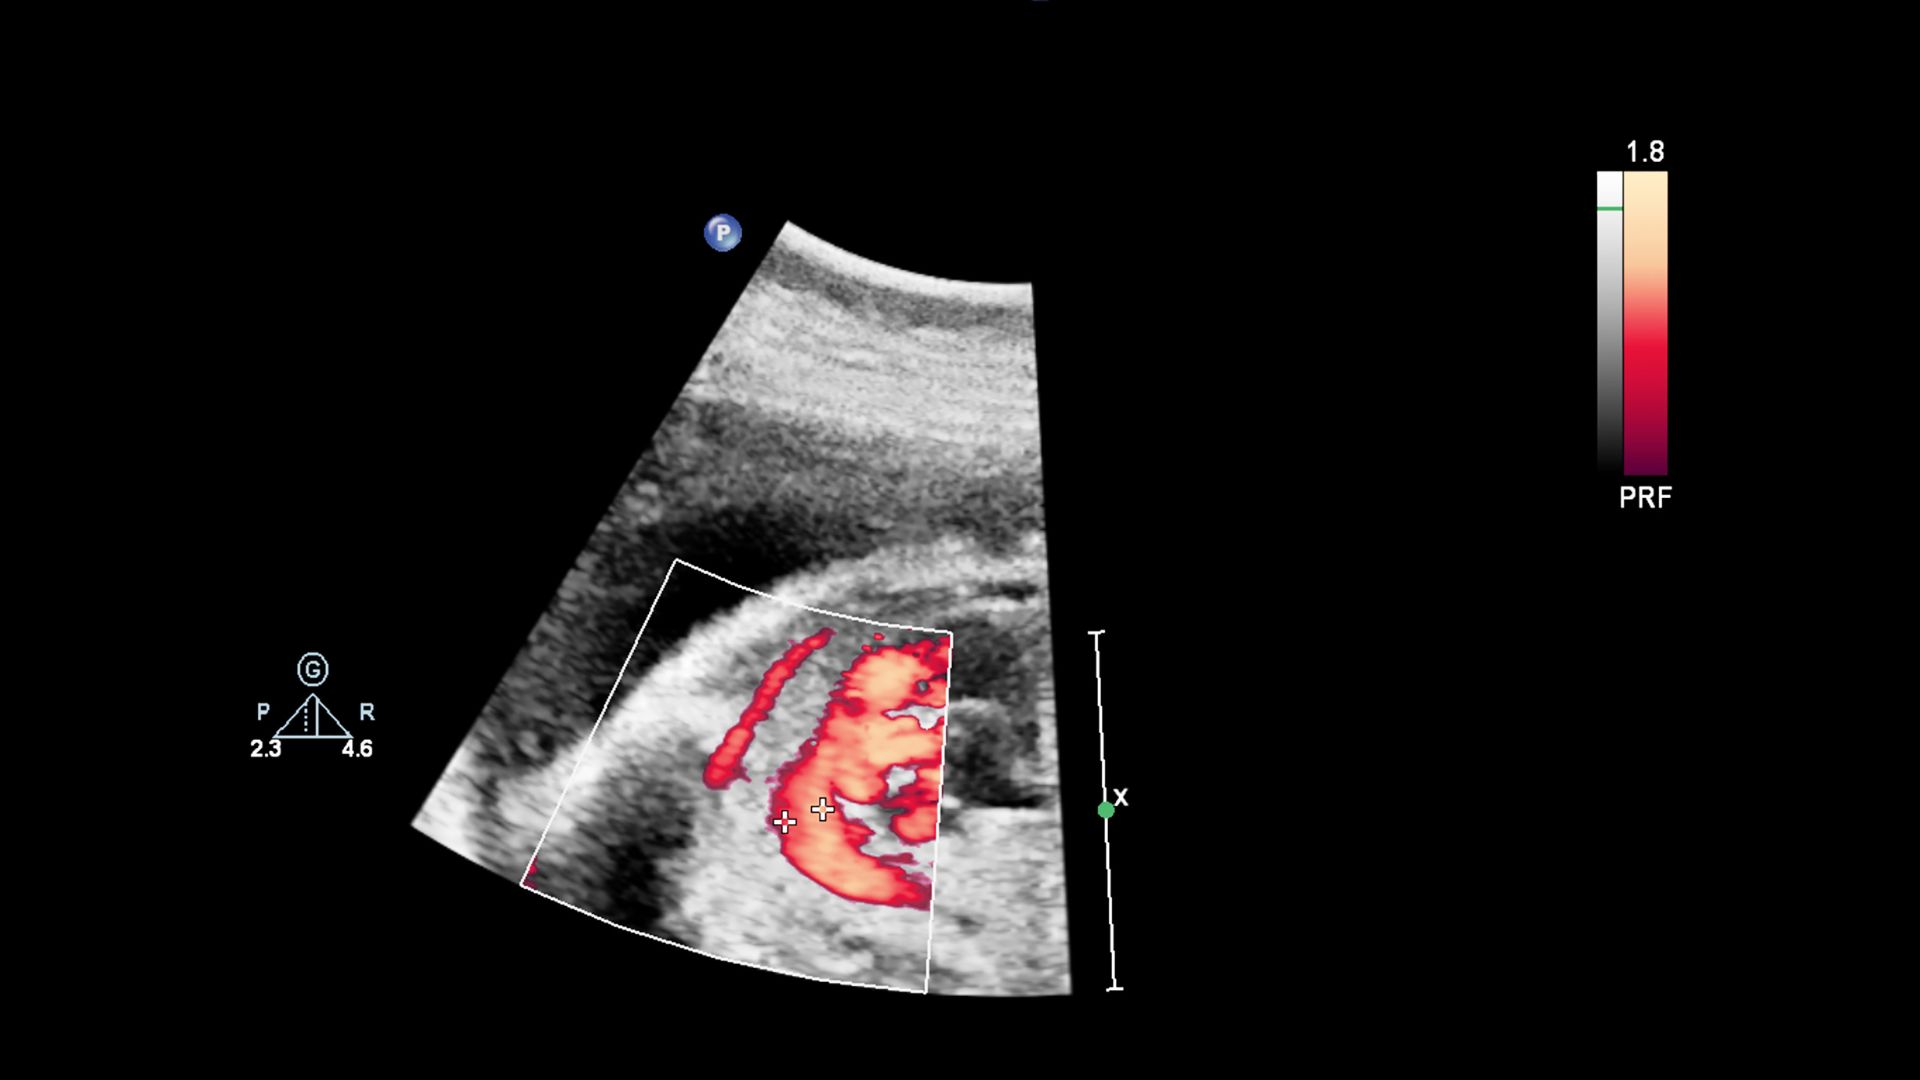

Siêu âm là phương pháp chính để đánh giá kích thước bể thận, lượng nước ối và sự phát triển chung của thai nhi. Khi phát hiện giãn, bác sĩ thường hẹn tái khám sau vài tuần để xem tình trạng có tiến triển hay ổn định.

Theo dõi liên tục giúp phân biệt giữa giãn sinh lý và giãn do tắc nghẽn thực sự. Nếu kích thước không tăng thêm và không có bất thường khác, khả năng cao là tình trạng nhẹ và có tiên lượng tốt.